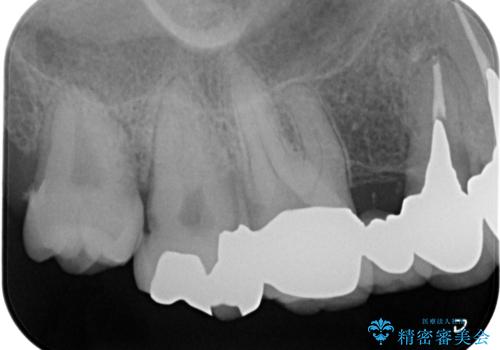

歯周ポケットの除去を併用したセラミック治療

- 歯周病や虫歯、歯の欠けなど多数の問題を他院で指摘され、今後長く持つように歯の問題をしっかりと解決したい。と希望され来院されました。

適合や審美性に優れるセラミック治療を行う前に、歯周病の問題を歯周外科を行うことで解決し将来的に不安のないような口腔内環境を整備していきます。

治療前に4-5mm程度あった歯周ポケットは全て2mm以内となり、非常に清掃性が高く、歯周病の再発しずらい環境に整えた上でのセラミック治療を実践することができました。